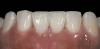

Growth-factor hydrated freeze-dried bone allograft.

Figure 2

Figure 14